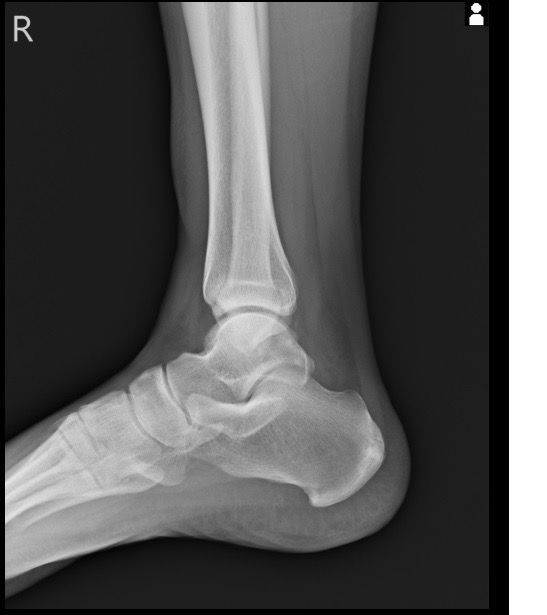

복숭아뼈 미세골절 초음파 사진 관련 질문

발목 접지른 후 치료받는 중인데요 복숭아뼈 미세골절이라고 하셨네요 3월 1일 다친뒤네 3월7일 병원방문후에 위에 초음파랑 엑스레이 촬영했고요 그뒤 반깁스 중입니다. 위에 엑스레이 상에선 안나오는데 초음파 사진에선 미세골절이 맞을까요? 골절이 경미한 수준인지 아니면 중한 건지 궁금합니다 그리고 다음주에 병원 방문 후 초음파 또 촬영하기로 했는데 그때 반깁스도 풀 수 있을까요??

발목의 복숭아뼈에 미세골절이 의심되는 경우, 엑스레이에서는 미세골절이 잘 보이지 않을 수 있습니다. 엑스레이는 큰 골절을 잘 확인하지만, 미세한 골절이나 염증 반응은 잘 나타나지 않기 때문이죠. 초음파는 조직의 변화를 보다 민감하게 감지할 수 있기 때문에, 미세골절을 발견하는 데 도움을 줄 수 있습니다. 초음파에서 미세골절이 확인되었다면, 이는 경미한 골절일 가능성이 높아요. 하지만 골절의 정확한 상태나 치유 과정을 판단하려면 정밀 검사가 필요하죠

미세골절의 치료는 시간이 필요하며, 반깁스를 착용하는 이유는 발목에 가해지는 부담을 줄이고, 골절 부위의 안정화를 돕기 위함입니다. 다음 병원 방문 시 초음파 촬영을 통해 골절의 치유 상태를 확인한 후, 의사가 반깁스를 풀어도 될지 결정할 듯 해요. 만약 골절이 잘 치유되었고 통증이 없다면 반깁스를 풀고 재활 운동을 시작할 수 있을 거구요. 하지만 치유가 더 필요한 경우에는 여전히 반깁스를 착용하거나 다른 치료 방법이 필요할 수 있겠죠